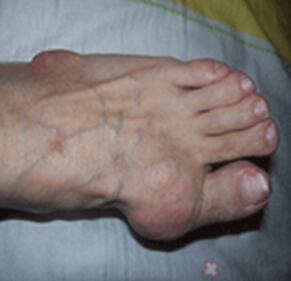

王怀庆主任经过对刘先生脚部痛风症状的观察,对其进行了详细的检查。诊断为痛风急性发作,刘先生右脚大脚趾关节红肿严重,左脚脚背大面积红肿,无法正常走路。尿酸值偏高,需立即降酸及修复功能处理,否则病...[详细]